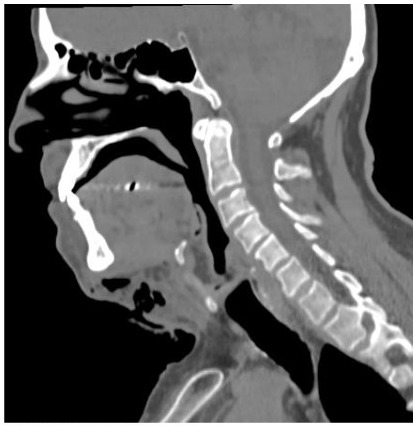

Um paciente de 55 anos, sexo masculino, apresentando quadro de infecção odontogênica complexa que ganhou espaços fasciais secundários foi internado em unidade hospitalar de emergência. Após Tomografia Computadorizada, foi observado em um corte sagital mediano a seguinte imagem. Ao analisá-la, assinale os itens abaixo.

I. O espaço submandibular encontra-se acometido e é observado na imagem.

II. A infecção envolve o espaço mediastinal.

III. O espaço pré-vertebral encontra-se acometido em nível da vértebra Cervical C3.